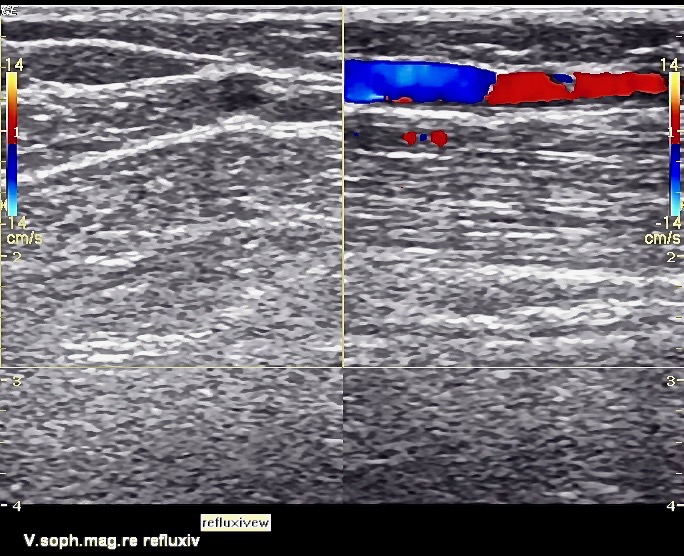

Duplex ultrasonography before surgery, the truncal varicose veins are free and can be treated well with vein glue

Basically, in addition to the clinical examination methods – the anamnesis, gaze diagnostics. and scanning – the methods of duplex ultrasound / Doppler sonography with color coding come into play. These give a very good picture of figure, extension, and veins involved (deep venous system!). And shows us quite quickly the possible treatment options. In addition to the normal laboratory values, a differentiated coagulation analysis and the search for a malignant tumor disease are indispensable.